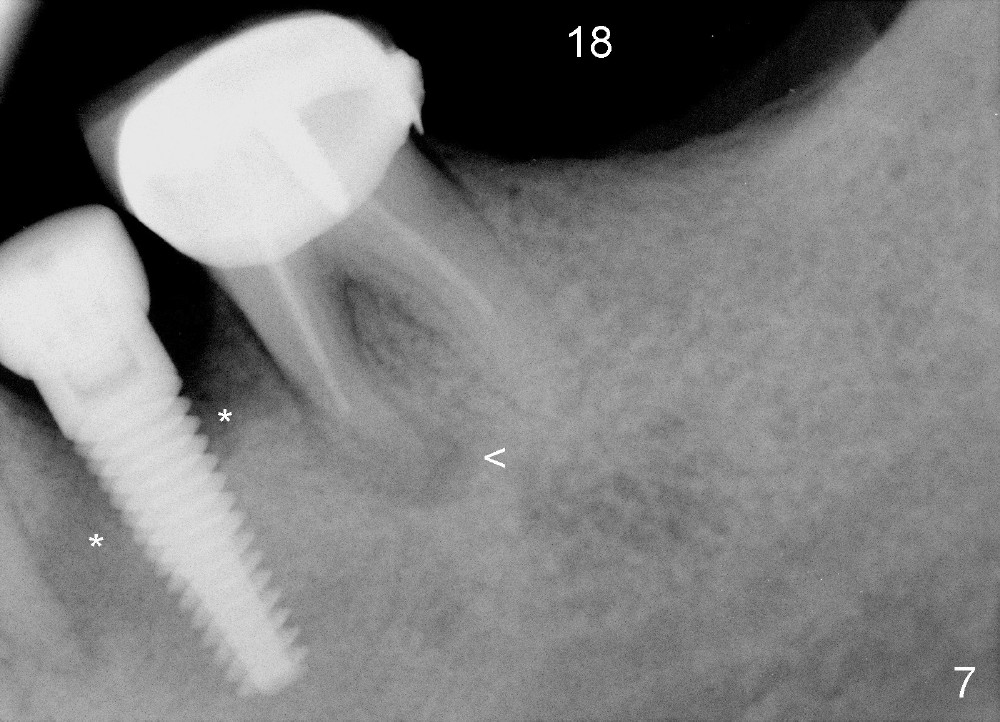

Four and a half months later, an implant is planned for #18 (Fig.7). The preop PA reveals that there is no bone growth around the implant at the site of #20, although the buccal swelling appears less prominent (Fig.8) than before (Fig.5). Without too much thinking, flap is raised for debridement (Fig.9). Autogenous bone graft is harvested from the site of #18 and placed in the defect area. By the time the surgery is done, the possible source becomes obvious: the periapical infection of the mesial root of #19 (Fig.10 arrowheads from primary infection to secondary one). Since there is also a furca lesion, possibly related to the post (P), the tooth has guarded to poor prognosis.